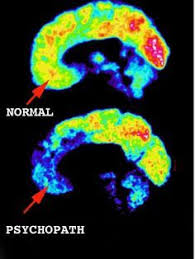

Click Here To Support Help Teach What Is A Psychopath By Tina Taylor Psychopath Brain Scan Abnormal Psychology

Life As A Nonviolent Psychopath Psychopath Brain Scan Psychology Facts